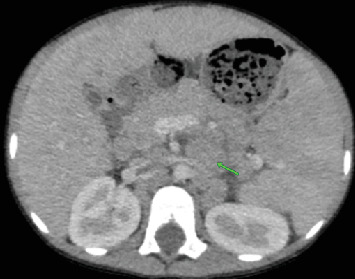

t细胞/组织细胞丰富的大b细胞淋巴瘤(THRLBCL)是弥漫性大b细胞淋巴瘤(DLBCL)的一种罕见的侵袭性亚型,在儿童中并不常见。在这里,我们提出一个8岁的男性病例,他有3个月的低度间歇性发热史,体重明显减轻,食欲不振,腹部肿胀。检查显示脾肿大,腹部中部可触及肿块,实验室结果显示双氧体减少。影像学显示肝脾肿大,弥漫性低密度肝脏和脾脏病变,肠系膜和腹膜后淋巴结病变。肠系膜肿块的核心穿刺活检证实了诊断,组织病理学显示分散的大单核和双核细胞,背景是小淋巴细胞和组织细胞。免疫组织化学显示CD45、CD20和EMA呈阳性,CD30、CD15和Bcl-2呈阴性,排除了其他诊断,如结节性淋巴细胞显性霍奇金淋巴瘤(NLPHL)和经典霍奇金淋巴瘤(cHL)。患者最初通过环磷酰胺、长春新碱和泼尼松(COP)的前期方案稳定,随后用R-COPADM(利妥昔单抗、环磷酰胺、长春新碱、泼尼松和甲氨蝶呤)诱导和巩固。治疗后影像学显示淋巴结病变和肝脾肿大明显消退,无残留或复发疾病。在随访中,患者仍处于临床缓解期,无进展迹象。该病例强调了早期识别,详细的组织病理学评估以及免疫组织化学在准确诊断儿童THRLBCL中的作用,确保及时开始有效治疗并改善这种罕见的儿科恶性肿瘤的预后。

T-cell/histiocyte-rich large B-cell lymphoma (THRLBCL) is a rare and aggressive subtype of diffuse large B-cell lymphoma (DLBCL) that is uncommon in children. Here, we present the case of an 8-year-old male with a 3-month history of low-grade intermittent fever, significant weight loss, loss of appetite, and progressive abdominal swelling. Examination revealed splenomegaly and a palpable midabdominal mass, with laboratory findings showing bicytopenia. Imaging demonstrated hepatosplenomegaly, diffuse hypodense liver and spleen lesions, and mesenteric and retroperitoneal lymphadenopathy. A core-needle biopsy of the mesenteric mass confirmed the diagnosis, with histopathology revealing scattered large mononuclear and binucleate cells in a background of small lymphocytes and histiocytes. Immunohistochemistry showed positivity for CD45, CD20, and EMA and negativity for CD30, CD15, and Bcl-2, excluding alternative diagnoses such as nodular lymphocyte-predominant Hodgkin lymphoma (NLPHL) and classical Hodgkin lymphoma (cHL). The patient was initially stabilized with a prephase regimen of cyclophosphamide, vincristine, and prednisone (COP), followed by induction and consolidation with R-COPADM (rituximab, cyclophosphamide, vincristine, prednisone, and methotrexate). Posttreatment imaging revealed significant resolution of lymphadenopathy and hepatosplenomegaly, with no residual or recurrent disease. At follow-up, the patient remains in clinical remission with no signs of progression. This case highlights the importance of early recognition, detailed histopathological evaluation, and the role of immunohistochemistry in accurately diagnosing THRLBCL in children, ensuring timely initiation of effective therapy and improving outcomes in this rare pediatric malignancy.